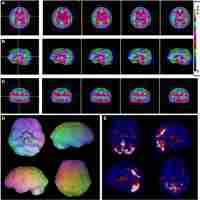

| Description | Journal: Human brain mapping Attention deficit hyperactivity disorder (ADHD) is a heterogeneous disorder with a strong genetic component. The norepinephrine transporter (NET) is a key target for ADHD treatment and the NET gene has been of high interest as a possible modulator of ADHD pathophysiology. Therefore, we conducted an imaging genetics study to examine possible effects of single nucleotide polymorphisms (SNPs) within the NET gene on NET nondisplaceable binding potential (BPND) in patients with ADHD and healthy controls (HCs). Twenty adult patients with ADHD and 20 HCs underwent (S,S)‐[18F]FMeNER‐D2 positron emission tomography (PET) and were genotyped on a MassARRAY MALDI‐TOF platform using the Sequenom iPLEX assay. Linear mixed models analyses revealed a genotype‐dependent difference in NET BPND between groups in the thalamus and cerebellum. In the thalamus, a functional promoter SNP (−3081 A/T) and a 5′‐untranslated region (5′UTR) SNP (−182 T/C), showed higher binding in ADHD patients compared to HCs depending on the major allele. Furthermore, we detected an effect of genotype in HCs, with major allele carriers having lower binding. In contrast, for two 3′UTR SNPs (*269 T/C, *417 A/T), ADHD subjects had lower binding in the cerebellum compared to HCs depending on the major allele. Additionally, symptoms of hyperactivity and impulsivity correlated with NET BPND in the cerebellum depending on genotype. Symptoms correlated positively with cerebellar NET BPND for the major allele, while symptoms correlated negatively to NET BPND in minor allele carriers. Our findings support the role of genetic influence of the NE system on NET binding to be pertubated in ADHD. Hum Brain Mapp 37:884–895, 2016. © 2015 The Authors Human Brain Mapping Published by Wiley Periodicals, Inc. |